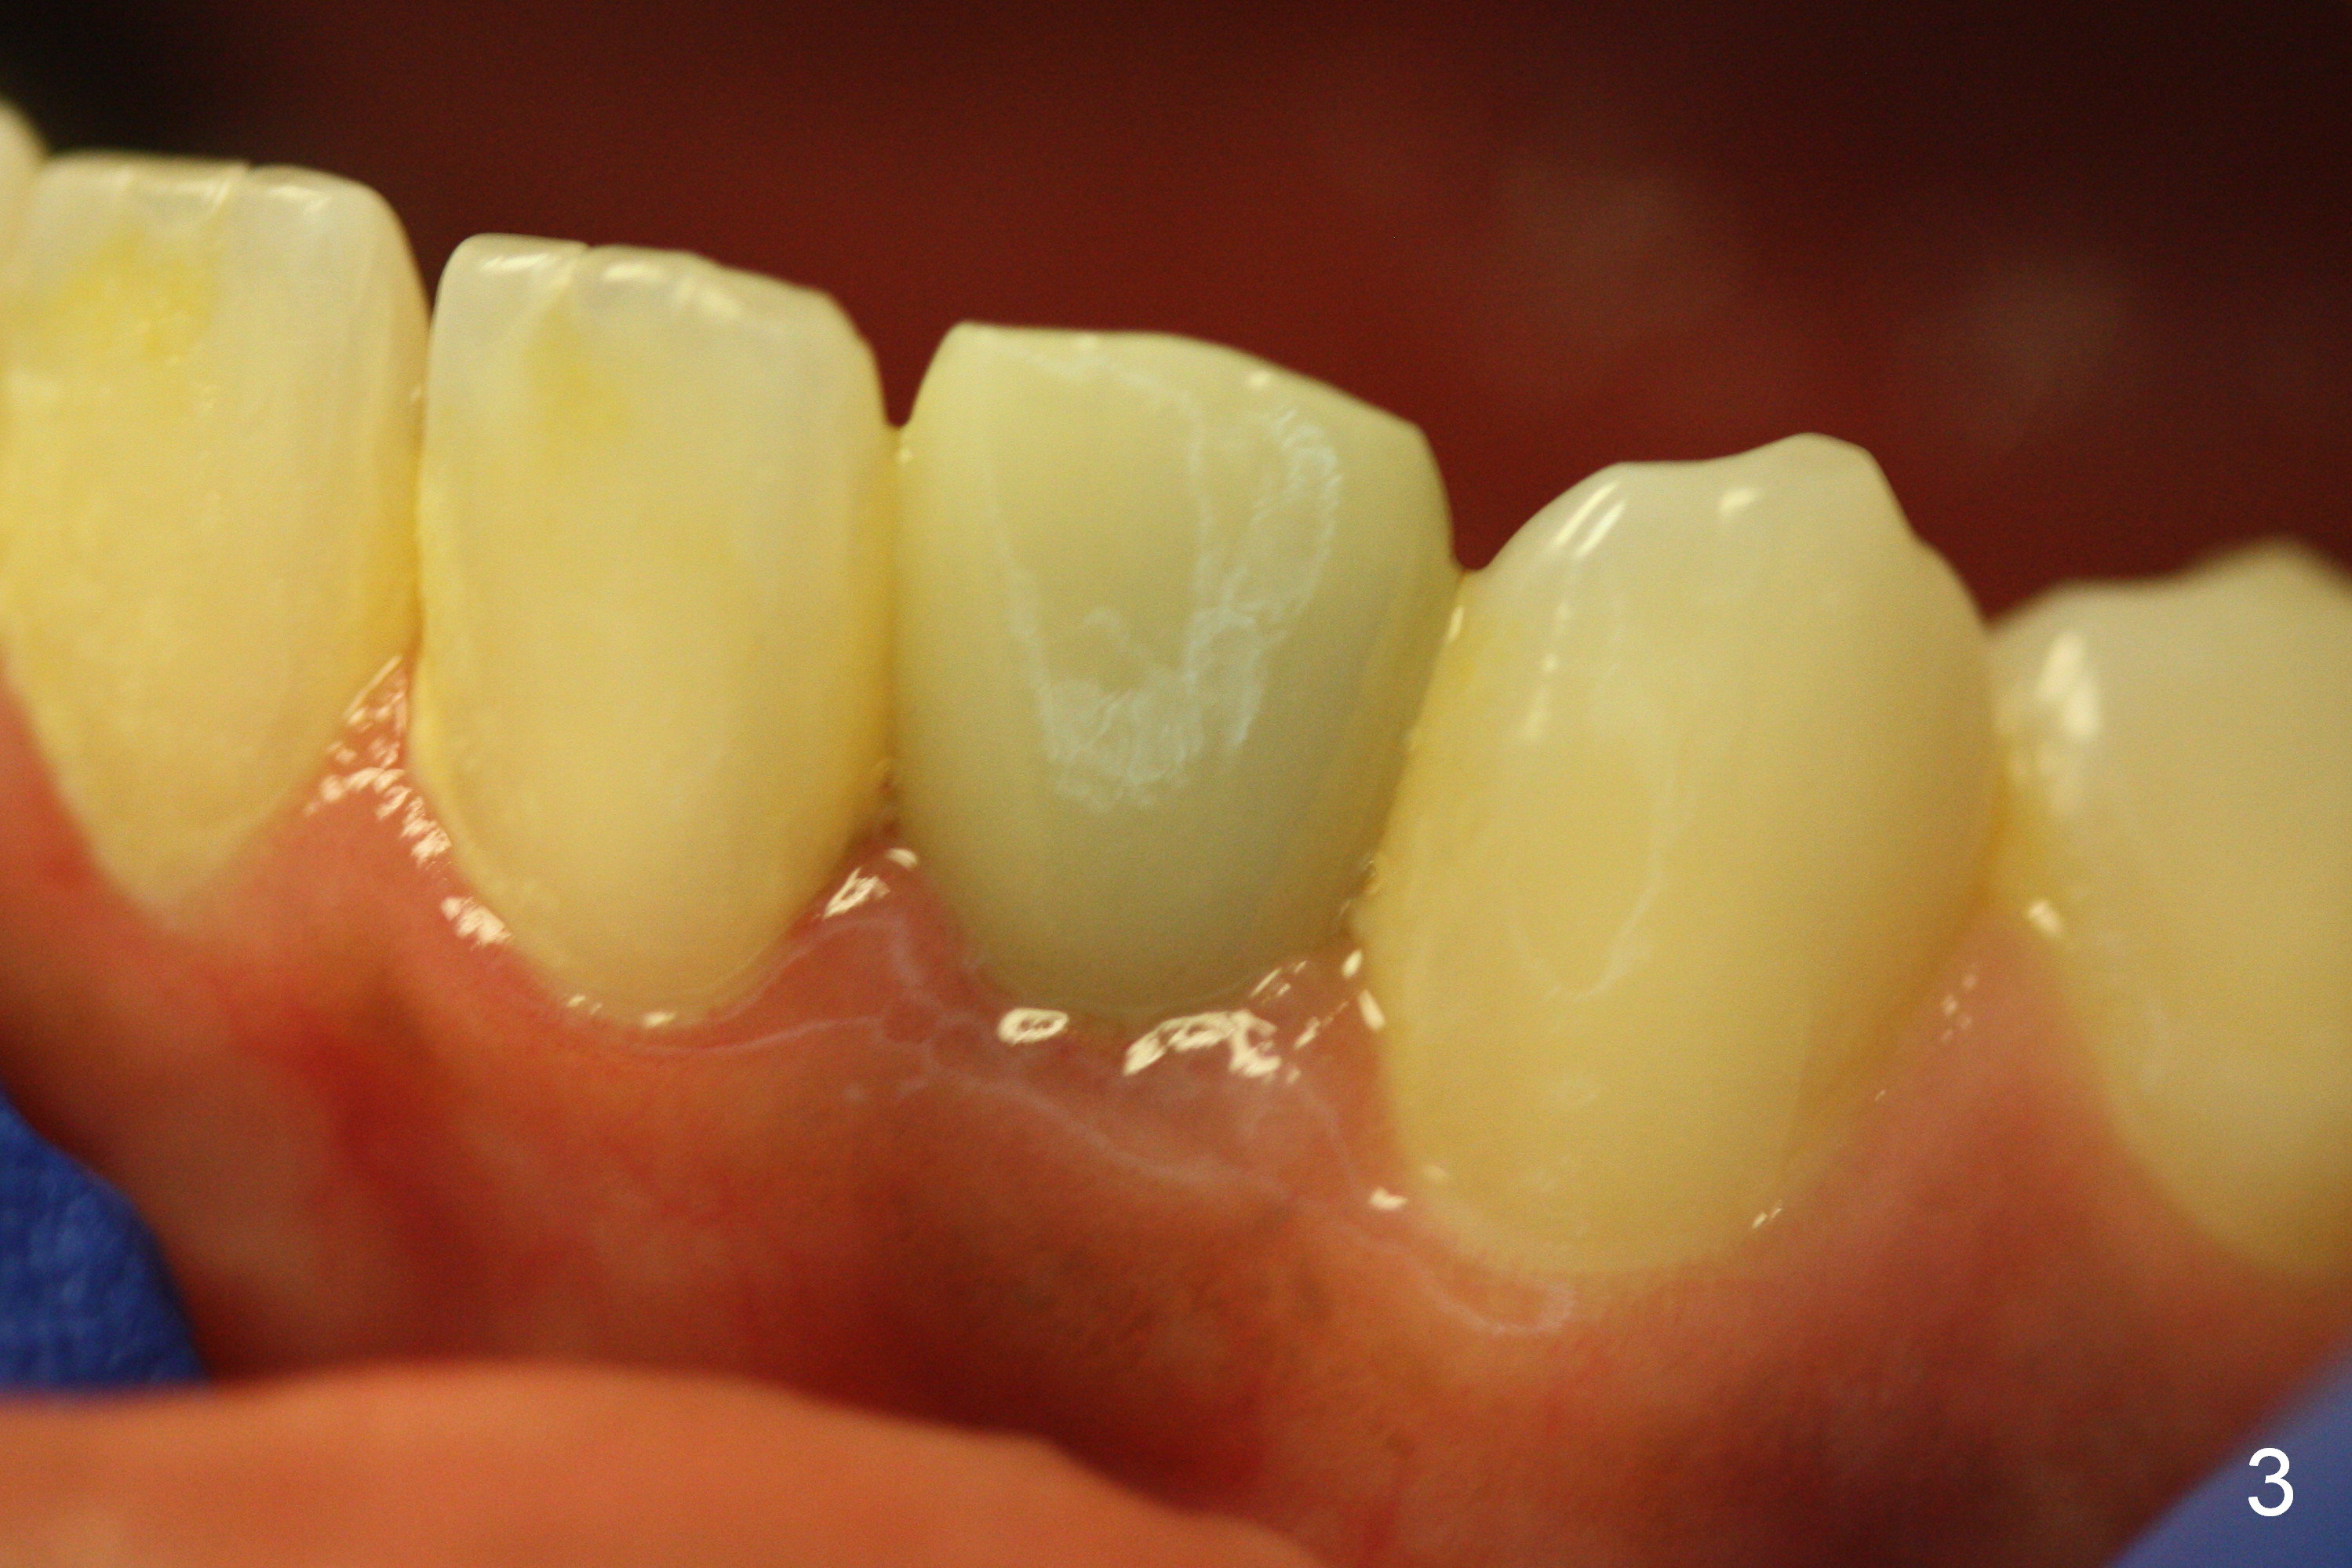

Make a new crown less transparent than the previous one (Fig.3). Can you block inside the crown to take care of the metal shade of the abutment/implant?

Choose a shade a little darker and more yellowish (Fig.4-7 before

cleaning; Fig.9-11 after cleaning). It

appears that there is a change in shade of crown over the time.

The patient is sure that the original shade was alright, but over the

time the shade changes. I wonder

whether it is due to stain/paint to the crown in the lab.

Can you choose a Zirconia block that has the closest shade?

Do not stain or paint the crown.